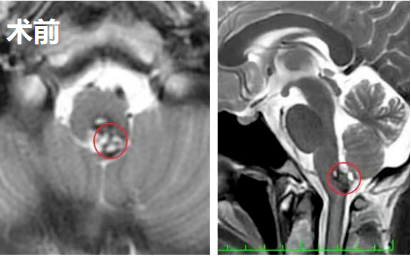

一个多月后,阿朔在苏州独墅湖医院进行了颅脑核磁共振检查。检查结果令人揪心:延髓(脑干下部关键区域)出现异常信号,高度提示“海绵状血管瘤”。

2022年11月27日,由巴特朗菲教授主刀,在国内神经外科团队的配合下阿朔延髓深处的海绵状血管瘤被成功完整切除。